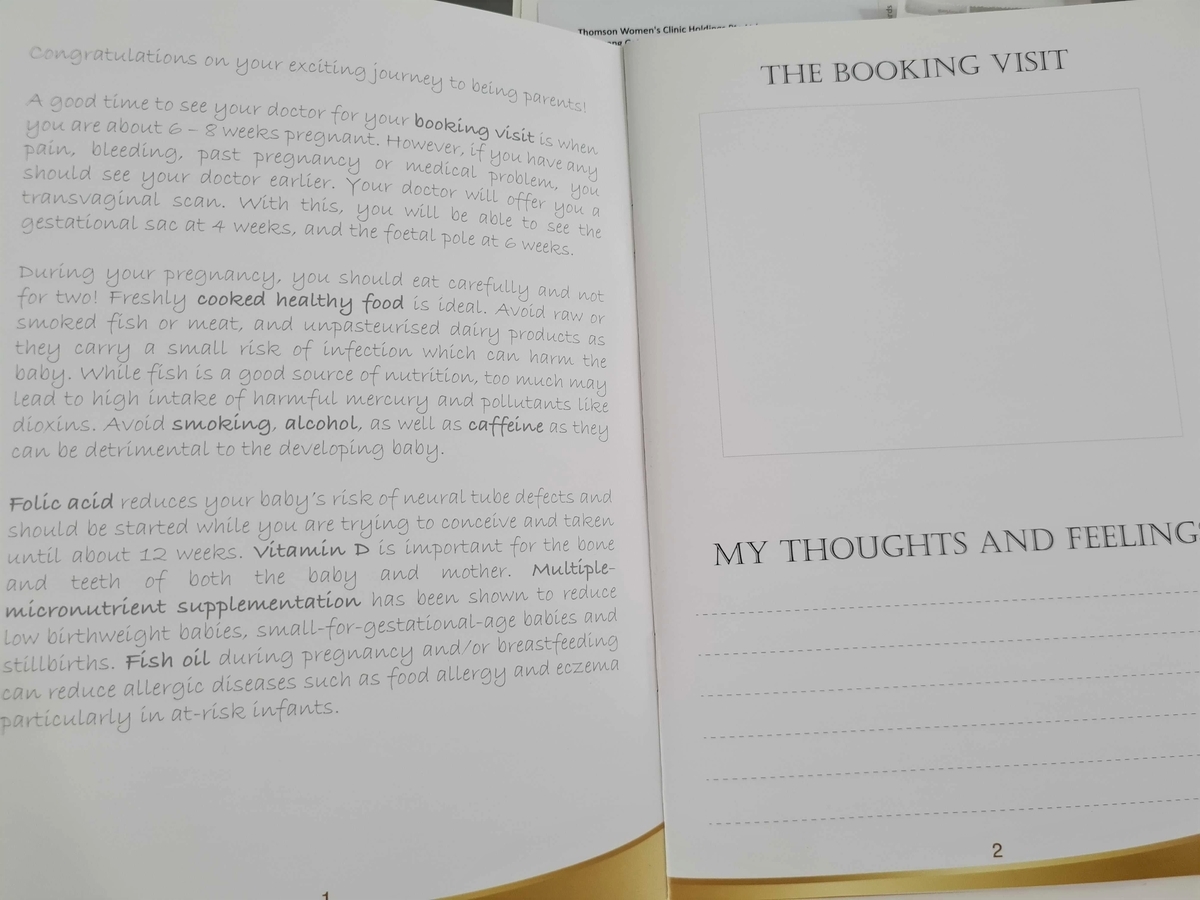

Pregnancy book というものをいただきました😊

"Congratulations on your exciting journey to being parents!"

アドバイスやその週に起こるマイナートラブル、エコー写真を貼れるページがあって日記代わりに使えそう😊

脳の機能や正常な成長に必要なサプリメント(Fish Oil)

食事だけではなかなか必要な栄養素を取っていくのは難しそうなので